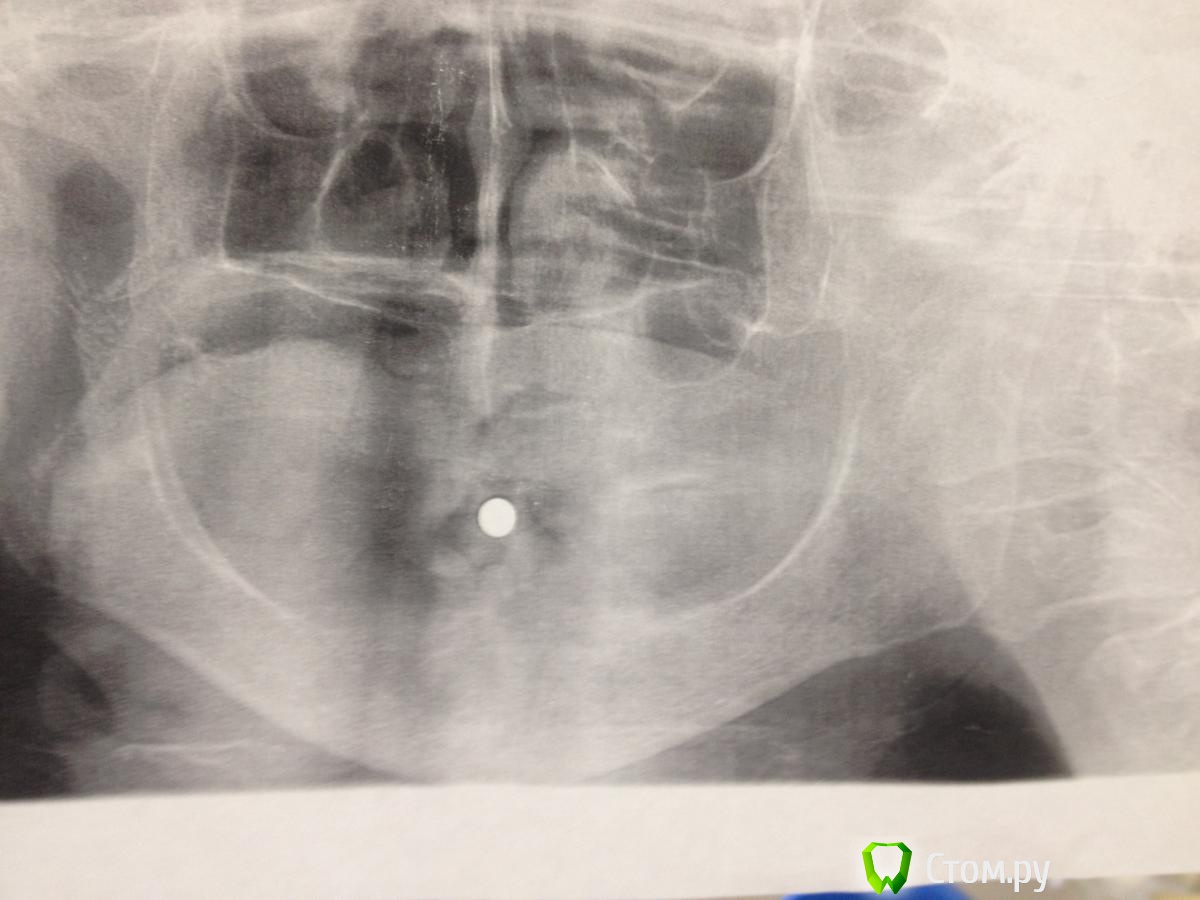

MaxDok Опубликовано 27 июня, 2014 Поделиться Опубликовано 27 июня, 2014 Всем добрый день !Пациенту 72 года. Интересует н.ч.,планируется установка 4 имплантов для фиксации съемного протеза . Кто каким путем пошел бы в данной ситуации ? Что можете посоветовать по оптг , ширина кости 2-3 мм . Ссылка на комментарий

kriokov Опубликовано 27 июня, 2014 Поделиться Опубликовано 27 июня, 2014 Всем добрый день !Пациенту 72 года. Интересует н.ч.,планируется установка 4 имплантов для фиксации съемного протеза . Кто каким путем пошел бы в данной ситуации ? Что можете посоветовать по оптг , ширина кости 2-3 мм . пусть хирурги повнимательней подбородок посмотрят от 44 до 34, там толщины кости обычно хватает.Свод сформировать можно во фронте тоже .Локаторы, самое простое. Ссылка на комментарий

red_butler Опубликовано 27 июня, 2014 Поделиться Опубликовано 27 июня, 2014 Часто проще со шлифовать до необходимой ширины, сделайте кт 4 Ссылка на комментарий

MaxDok Опубликовано 28 июня, 2014 Автор Поделиться Опубликовано 28 июня, 2014 (изменено) пусть хирурги повнимательней подбородок посмотрят от 44 до 34, там толщины кости обычно хватает. Свод сформировать можно во фронте тоже . Локаторы, самое простое.Спасибо ,хирург говорит там вообще не куда , миники только во фронте не будут нормально работать ИМХО , но я передам ))Свод Вы имеете вестибулопластику сделать ? Да локаторы попроще , но учитывая атрофию , думаю нужно что то "пожещще" в плане фиксации Изменено 28 июня, 2014 пользователем MaxDok Ссылка на комментарий

MaxDok Опубликовано 28 июня, 2014 Автор Поделиться Опубликовано 28 июня, 2014 Часто проще со шлифовать до необходимой ширины, сделайте ктТак иногда делали , но тут видимо некуда уже сошлифовывать , природа постаралась за нас Хотя это мое дилетантское мнение . На кт отправим объязательно. Ссылка на комментарий